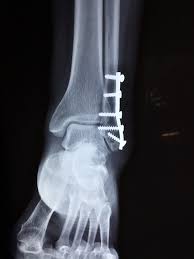

Fraktur oberhalb der verletzen Syndesmose Membrana interossea häufig auch rupturiert Die Maisonneuve-Fraktur wird als Sonderform der Sprunggelenksfraktur auch als Weber C klassifiziert. This normally takes approximately 6 weeks to heal. Die Weber-Klassifikation eine Methode zur Beschreibung von Sprunggelenksfrakturen.

KLASIFIKASI FRAKTUR WEBER Drsimon ponco septiono f Weber A Garis fraktur berada dibawah syndemiosis thibiofibularis f Weber B Garis fraktur berada setinggi syndemiosis thibiofibularis f Weber C Garis fraktur berada diatas syndemiosis thibiofibularis f. Weber C Fraktur immer Weber A- und Weber B- Frakturen mit. Many translated example sentences containing Weber c Fraktur English-German dictionary and search engine for English translations.

Weber C Fraktur. Neben der Weber C Fraktur gibt es auch noch die Fraktur der Klasse A und B. Was ist eine Weber-C-Fraktur. DayZ sa well kit DayZ Expansion Building Kits - YouTub. Verschobenem Bruch dislozierte Fraktur undoder. It has a role in determining treatment. Weber C Fraktur. Look up the French to German translation of weber c fraktur in the PONS online dictionary. The Weber ankle fracture classification or Danis-Weber classification is a simple system for classification of lateral malleolar fractures relating to the level of the fracture in relation to the ankle joint specifically the distal tibiofibular syndesmosis.